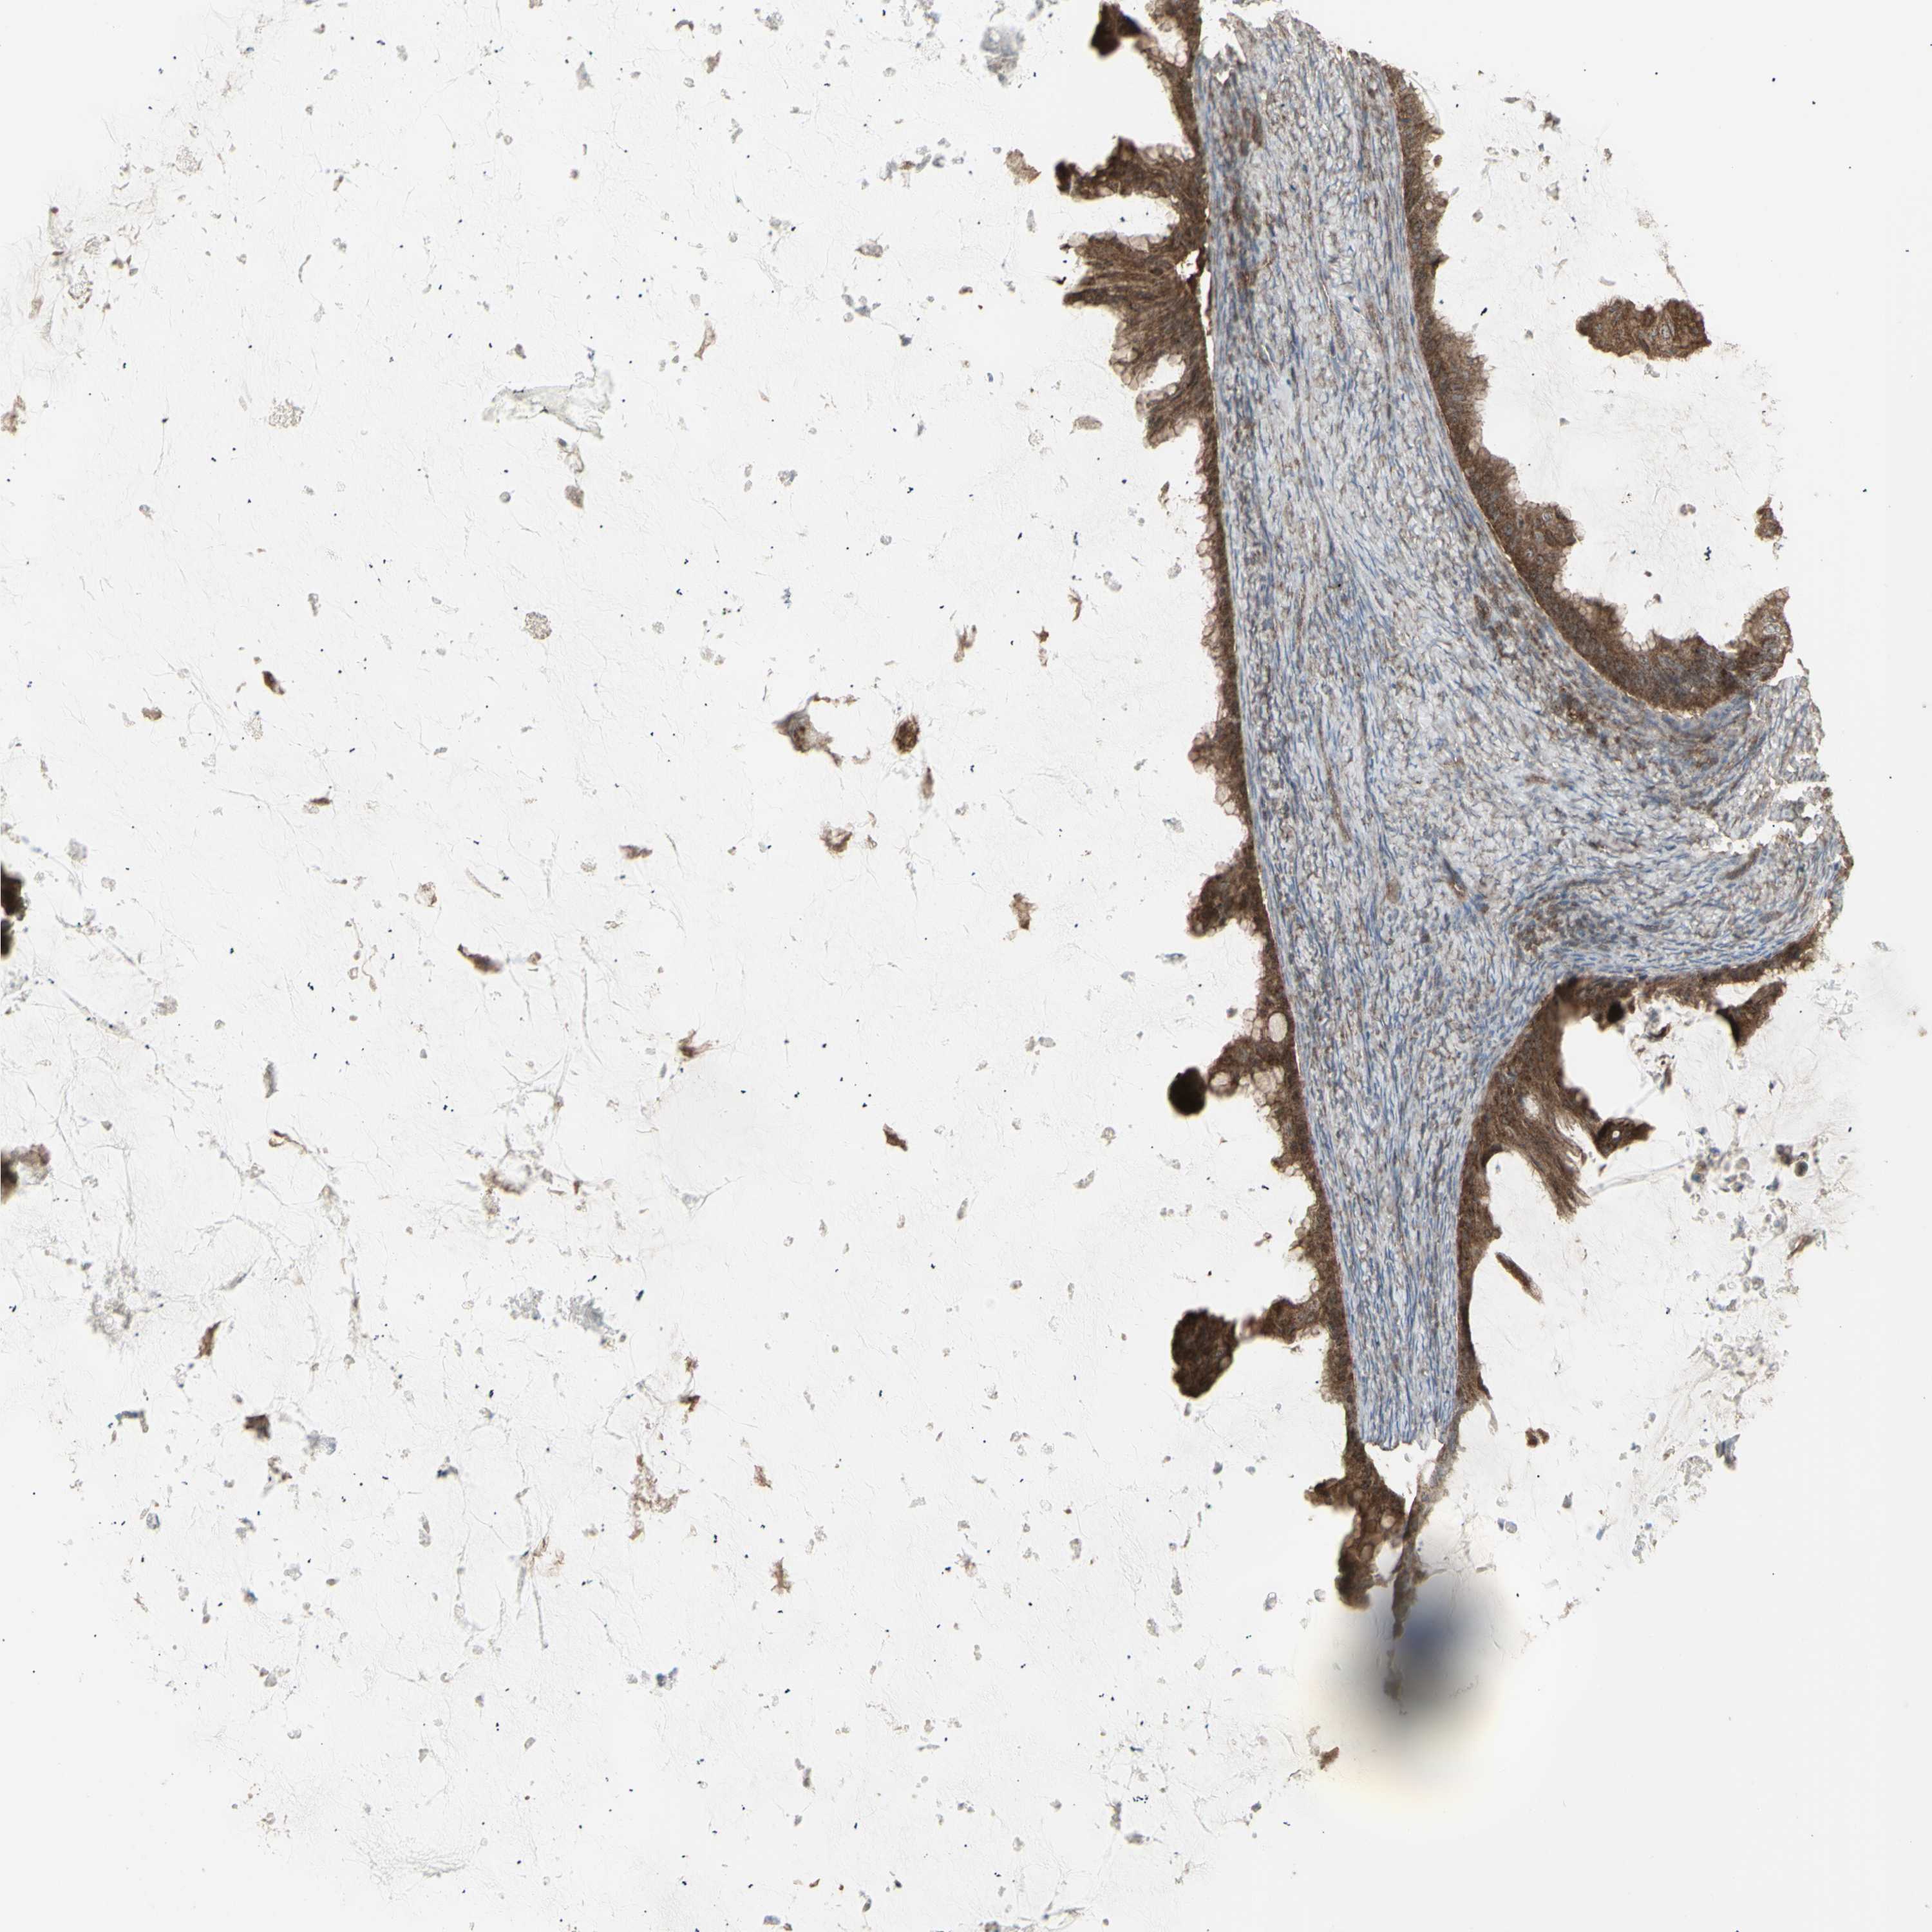

OVARIAN CANCER - Protein expressioni

A mouse-over function shows sample information and annotation data. Click on an image to view it in a full screen mode. Samples can be filtered based on level of antibody staining by selecting one or several of the following categories: high, medium, low and not detected. The assay and annotation is described here.

Note that samples used for immunohistochemistry by the Human Protein Atlas do not correspond to samples in the TCGA dataset.

Antibody stainingi

Antibody staining in the annotated cell types in the current human tissue is reported as not detected, low, medium, or high, based on conventional immunohistochemistry profiling in selected tissues. This score is based on the combination of the staining intensity and fraction of stained cells.

Each image is clickable and will lead to virtual microscopy that enables deeper exploration of all samples and also displays staining intensity scores, fraction scores and subcellular localization as well as patient and tissue information for each sample.

Antibody HPA002633

Antibody HPA046758

Antibody CAB010906

Carcinoma, endometroid

Cystadenocarcinoma, serous, NOS

Cystadenocarcinoma, mucinous, NOS

Carcinoma, NOS